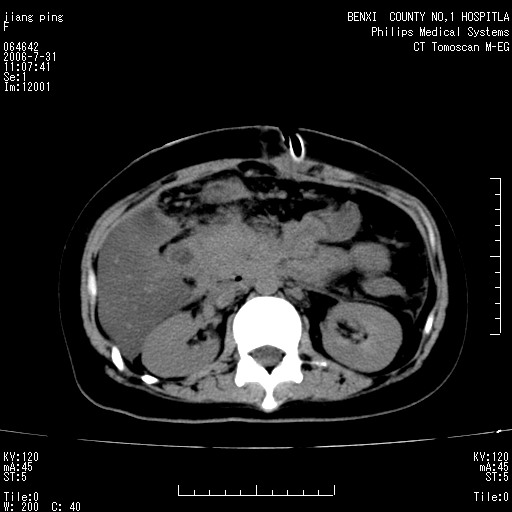

以下是引用晓杰在2006-8-1 9:01:00的发言:[br]支持营养不良导致脂肪肝。[br]胰头增大界限不清,考虑为胰腺炎破坏十二指肠粘膜、肠壁增厚、肠腔狭窄,并与胰头粘连所致

以下是引用jiajie在2006-7-31 20:34:00的发言:[br]支持营养不良导致脂肪肝。[br]胰头增大界限不清,考虑为胰腺炎破坏十二指肠粘膜、肠壁增厚、肠腔狭窄,并与胰头粘连所致。